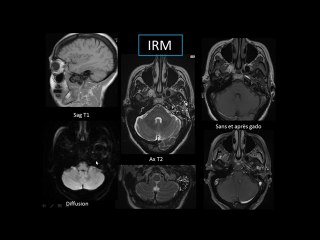

User: Technologie